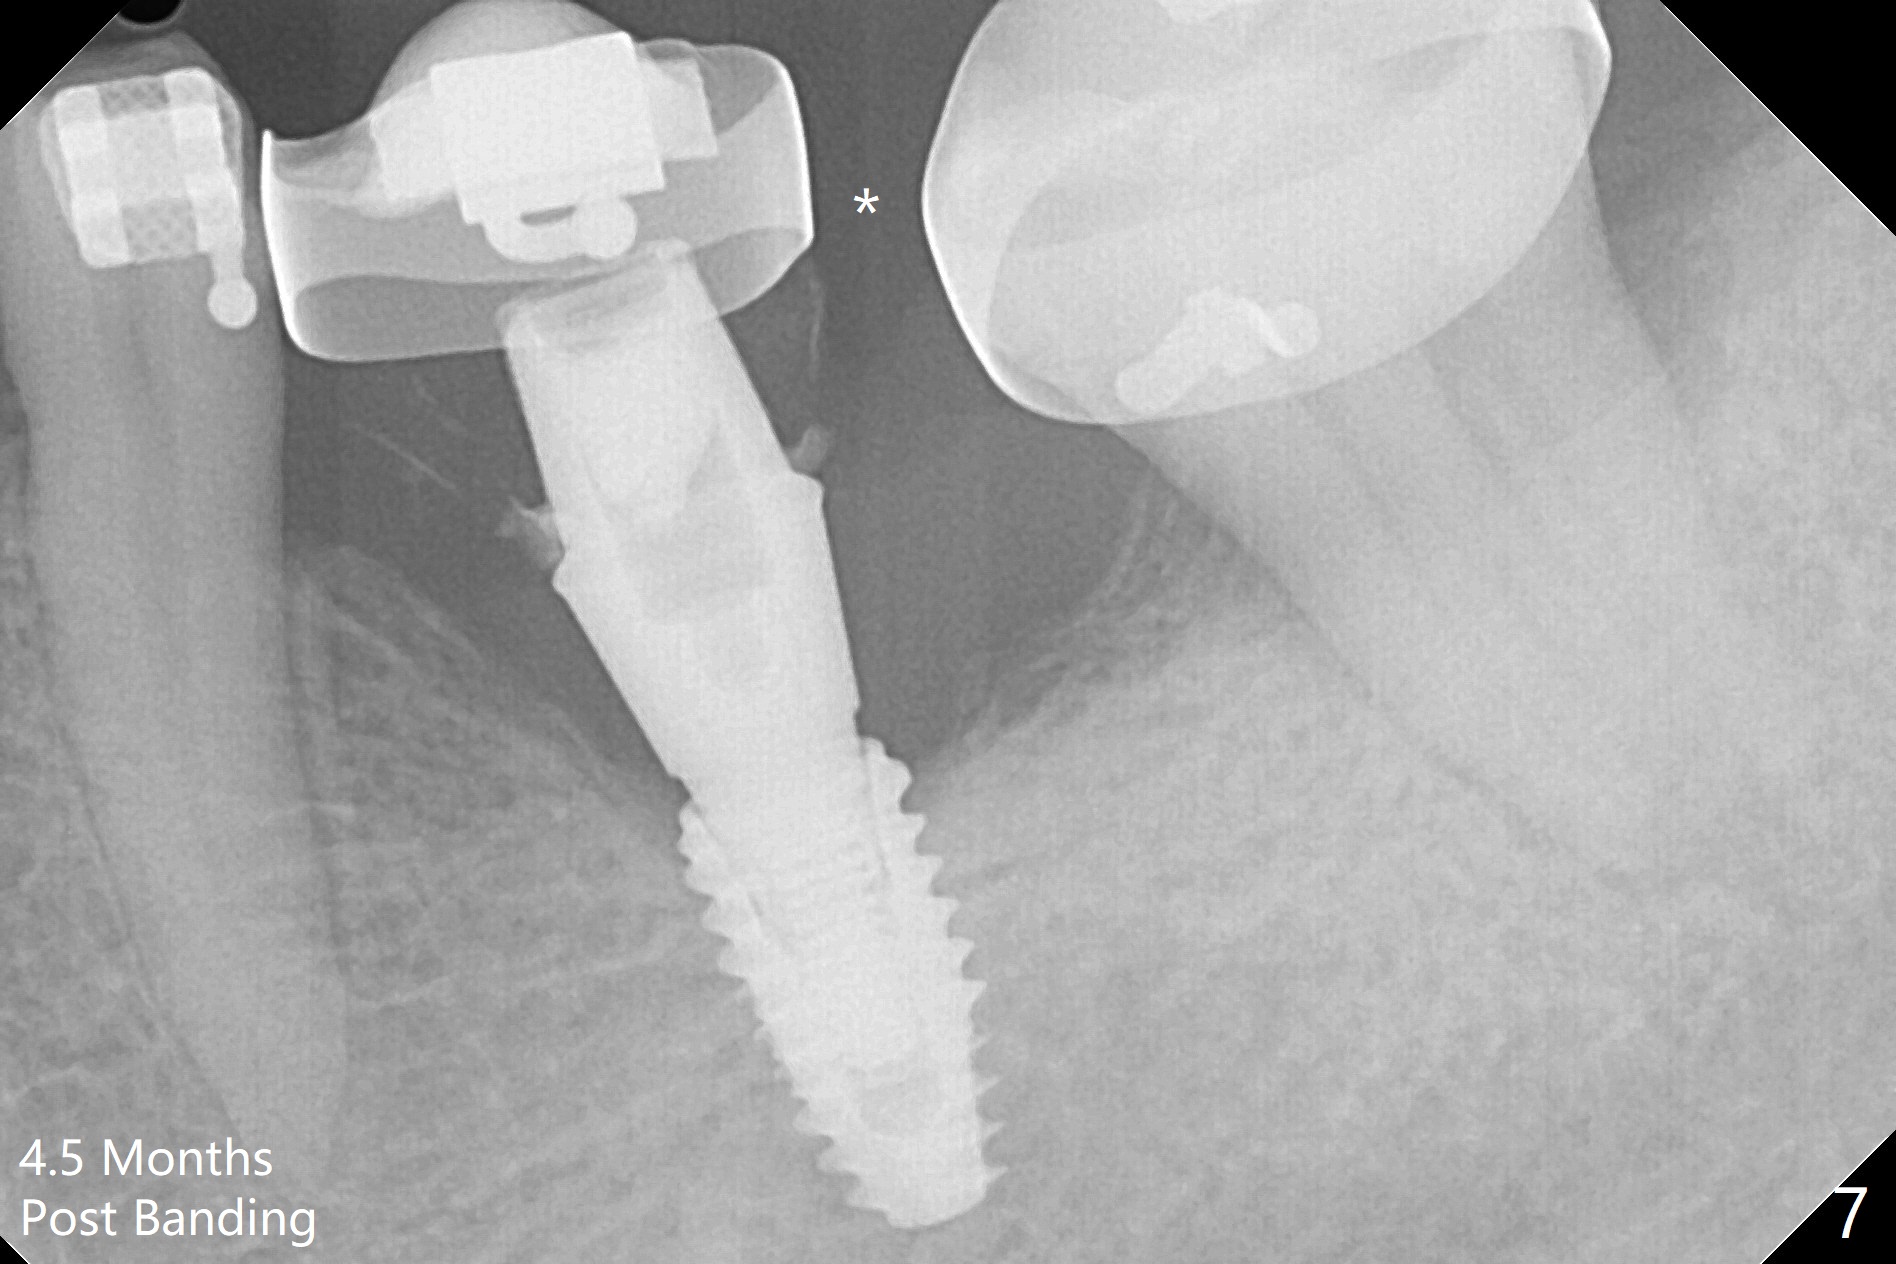

With 34 mg of Lidocaine and 17 mcg of Epinephrine (local infiltration), a 4.5x8.5 mm implant is placed with guide. The insertion torque is ~50 Ncm. It is placed in precise depth and in a short period of time (tolerable to the operators and patient, easier than mini-implant placement, Fig.1). There is no postop pain or paresthesia. The mesidistal position is within treatment plan (Fig.2). Miniimplants are placed to intrude #14 14 days prior. The teeth #16,17 and 32 are extracted 3 months postop. Minimal bone resorption at the crest is noted nearly 4 months postop (Fig.3). Bands and brackets are placed #18 upright 4 months postop (Fig.4 (14 niti wire)). The buccal and lingual view of the preop model shows that the supraerupted 1st molar (#14) has close relationship with the distal surface of the tooth #20 (Fig.5,6), accounting for the severe wear of the latter (Fig.8-11). The implant not only acts as an anchor to upright #18 in 4.5 months post banding (Fig.7 *), but also as an occlusal stop so that #18 has no interference to be moved. The stress on the implant results in radiating trabecular pattern (Fig.7,11 (9,11 months postop), as compared to before loading (Fig.1,3)). Restoring the distal contour of #20 with composite (Fig.12 C) makes it easy to close the space by adding porcelain the mesial surface of the implant crown. The crown/abutment is loose in China 7 months post cementation.